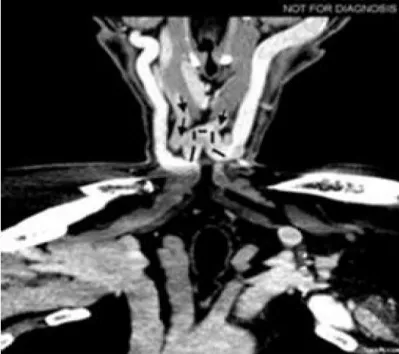

Clinical examination revealed a soft, compressible, painless mass on suprasternal space. The overlying skin was intact, and no lymphadenopathy was palpable. ENT and oral examination were normal. Clinical assessment clearly suggested a benign venous mass. A computed tomography angiography (CTA) of the head and neck was requested to expedite the diagnosis. The axial CTA of the root neck in the venous phase showed a median cervical swelling corresponding to a vein communicating between the two anterior jugular veins (Figure 2). The reconstruction in the coronal plane confimed an enlarged JVA (Figure 3).